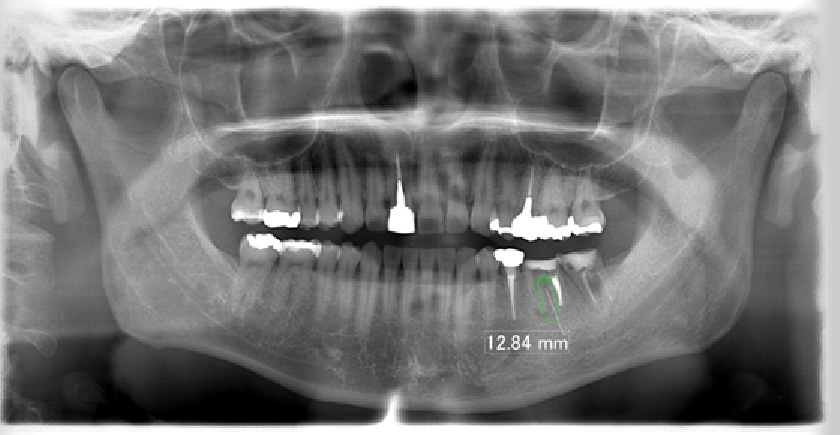

• 術前術後のレントゲン写真

写真向かって、右下の奥歯が割れてしまっているので、抜歯し、そこに人工歯根として、インプラントを埋め込んだレントゲン写真です。

• 術前

術前